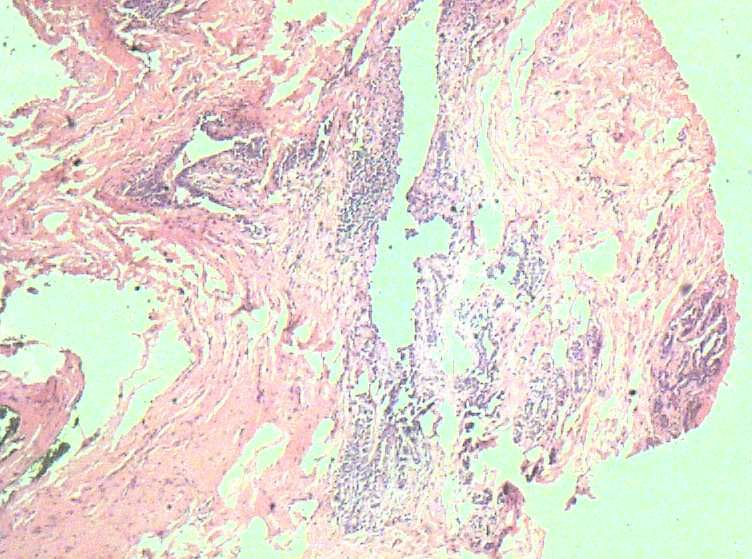

B3774乳腺积乳性包块?

女41岁,左腺包块。肉眼:不整形囊壁样组织,大小2*1.6*0.3CM,壁厚0.1—0.3,未触及结节,未见出血及坏死。

标签:乳腺纤维囊性增生症

似乎有导管扩张、慢性炎细胞浸润、大汗腺化生、普通型导管增生等病变,没有看到囊壁内衬上皮或囊壁结构。

乳腺腺病伴普通型导管增生